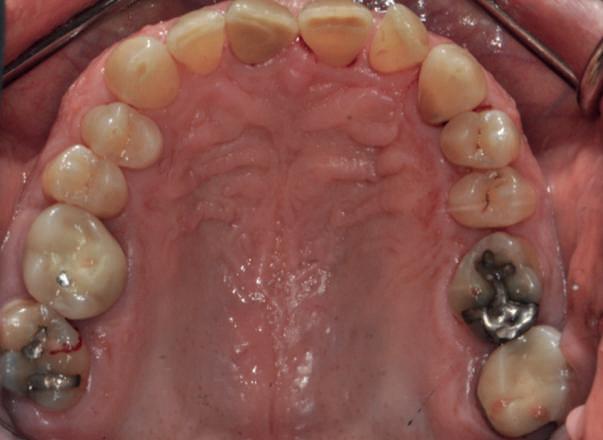

Examinarea parodontală a relevat sângerări generalizate la sondare și adâncimi de sondare de până la 9 mm la molarii maxilari și mandibulari, cu multiple furcații implicate la fiecare molar (fig. 2-7). Prezenta mobilitate multiplă de clasa I la dinții posteriori și de clasa II la dinții nr. 16 și 21 (molarul prim maxilar drept și incisivul central maxilar stâng).

Parodontologul a decis să evalueze dintele nr. 16 în privința PRS, deoarece acesta era molarul cel mai afectat parodontal care urma să fie tratat și menținut pe arcadă (fig. 2 și fig. 8). Acest dinte (molarul prim maxilar drept = scor 1) prezenta adâncimi de sondare de 7 mm (scor 1); trei invazii totale de furcație (scor 3) (mezial [furcație de grad II], vestibular [furcație de grad I] și distal [furcație de grad II]); și mobilitate de clasa II (scor 2). Valoarea totală a PRS pentru dintele 16 a fost de 8, reprezentând un prognostic „rezervat”. Pe baza acestui scor, probabilitatea de a nu pierde niciun dinte din cauza bolii parodontale timp de 15 ani a fost de 81%, iar pentru 30 de ani probabilitatea a fost de doar 56% (fig. 9).

2-4. Imagini înainte de tratament: lateral dreapta (fig. 2), frontal (fig. 3) și lateral stânga (fig. 4). Notă: Molarul prim maxilar drept (dintele 16) (fig. 2) ar fi identificat ca fiind molarul cel mai afectat parodontal care era planificat să fie menținut.

Figurile:

5, 6. Imagini ocluzale înainte de tratament: maxilar (fig. 5) și mandibulă (fig. 6).

7. Rx periapicale înainte de tratament.

8. Rx periapicală a molarului prim maxilar drept (identificat ca fiind molarul cel mai afectat parodontal care era planificat să fie menținut pe arcadă).